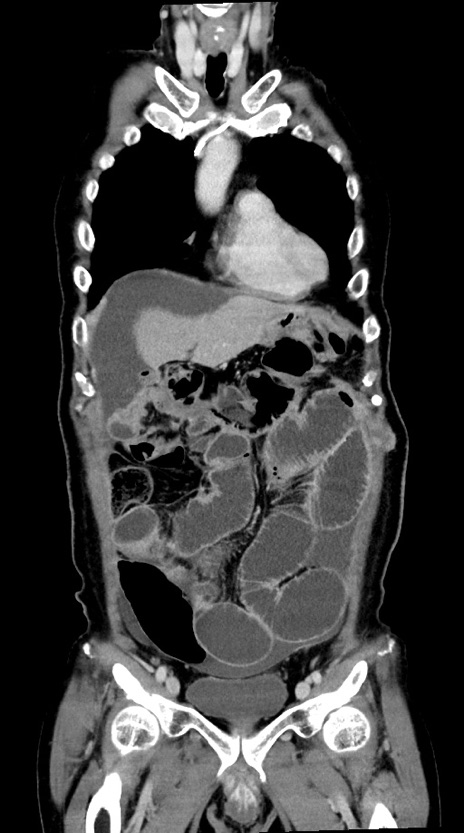

症例28(冠状断像)

【症例】60歳代男性

【主訴】嘔吐

【現病歴】胃癌にて胃全摘後。食思不振が悪化し、夜中に嘔吐することがある。

【既往歴】胃癌、胃全摘、脾摘、胆摘後

【データ】WBC 5900、CRP 10.56